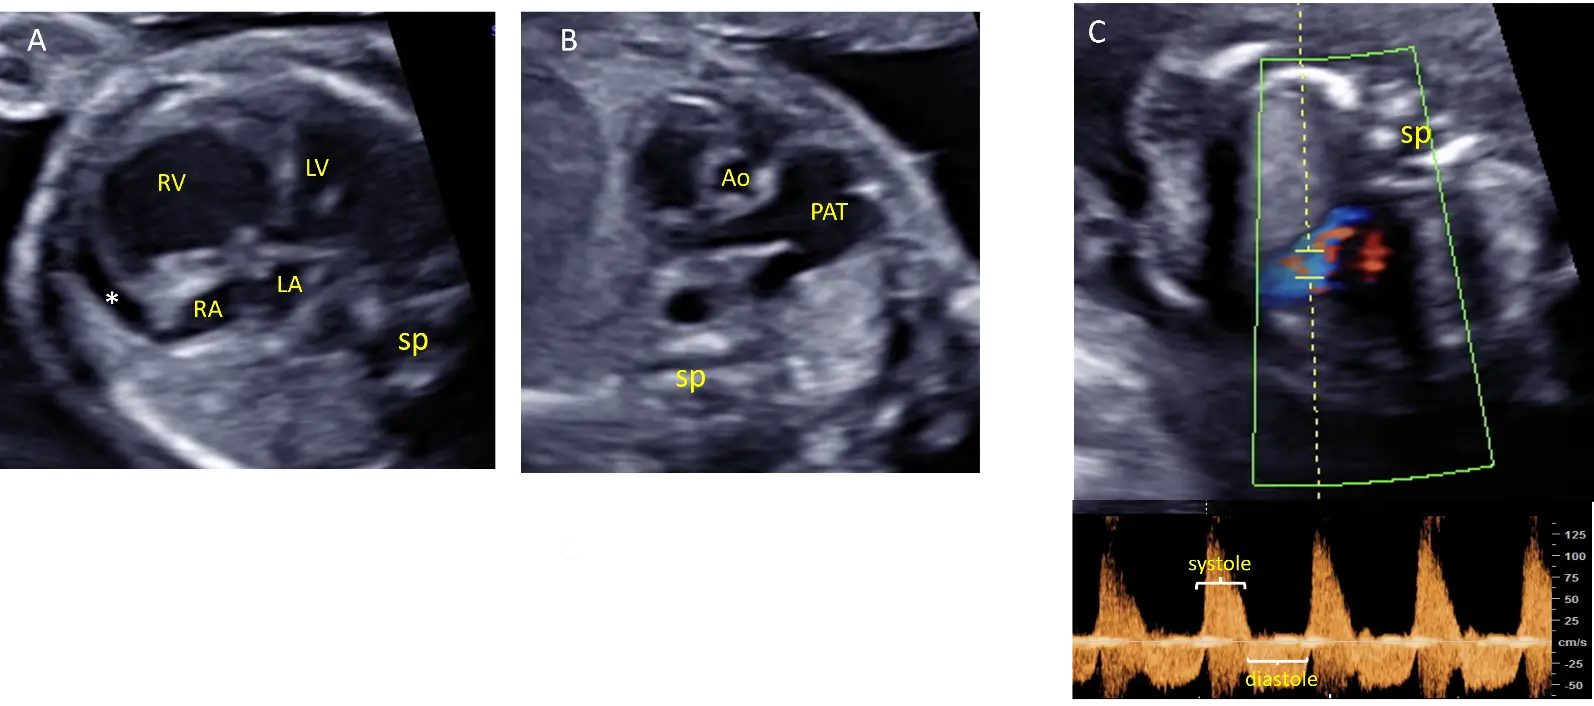

A 30-year-old woman in her first pregnancy was referred for evaluation at 22 weeks of pregnancy because of cardiomegaly and ventricular asymmetry. An ultrasound study confirmed a significant dilatation of the right ventricle. The absence of the pulmonary valve was characterized by a to-and-fro flow through both the pulmonary orifice and the ductus arteriosus. The pulmonary trunk showed significant dilatation, but the pulmonary branches were unaffected. Additionally, a pericardial effusion was observed (Figure 3). There was no tricuspid regurgitation. Amniocentesis with CGH yielded normal results.

Figure 3. Echocardiographic views from case #3 at 22 weeks of gestation: Four chamber view showing cardiomegaly with dilatation of the right ventricle and pericardial effusion (*) adjacent to dilated right cavities (A). Short axis view of the great arteries showing dilatation of the pulmonary artery trunk (PAT) but not of the pulmonary branches (B). Pulsed doppler showing a to-and-fro flow through the pulmonary annulus demonstrating pulmonary insufficiency (C). Ao: Aorta, LA: Left atrium, LV: left ventricle, RA: right atrium, RV: right ventricle, sp: spine.